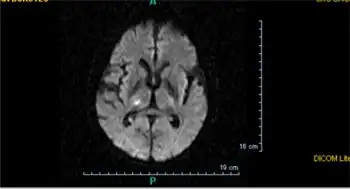

A silent lacunar infarction (SLI) is one type of silent stroke which usually shows no identifiable outward symptoms, and is thus termed "silent." Because stroke is a clinical diagnosis (that is, it is defined by clinical symptoms), there is debate about whether SLI are considered to be strokes, even though the pathophysiology is presumably the same. Individuals who have a SLI are often completely unaware they have had a stroke. This type of stroke often causes lesions in the surrounding brain tissue that are visibly detected via neuroimaging techniques such as MRI and computed axial tomography (CT scan). Silent strokes, including silent lacunar infarctions, have been shown to be much more common than previously thought, with an estimated prevalence rate of eleven million per year in the United States. Approximately 10% of these silent strokes are silent lacunar infarctions. While dubbed "silent" due to the immediate lack of classic stroke symptoms, SLIs can cause damage to the surrounding brain tissue and can affect various aspects of a person's mood, personality, and cognitive functioning. A SLI or any type of silent stroke places an individual at greater risk for future major stroke.[7][8]

In terms of the diagnosis of a stroke of this nature, the following is done:[12]

- CT scan

- MRI

- CT angiogram